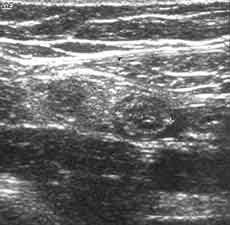

Рис. 6 и 7. (Слева) Воспаленный аппендикс в продольном сечении. Положение датчика косое. (Справа) Поперечное сканирование воспаленного изогнутого (на снимке дважды видно поперечное сечение) аппендикса.